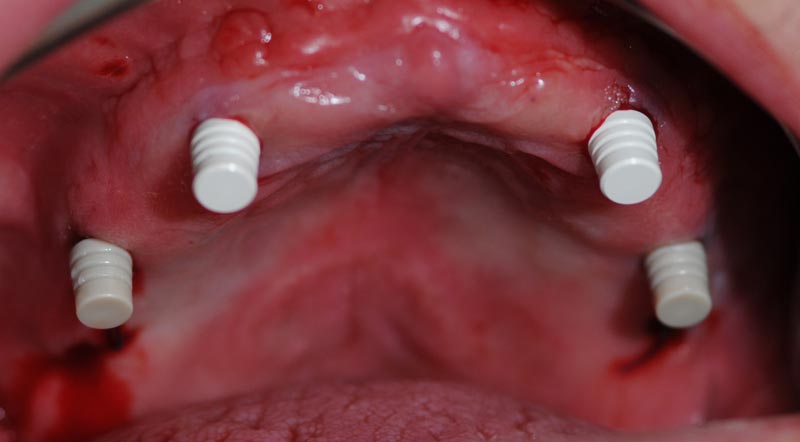

Impianti posizionati

Posizionamento dei MUA negli impianti in base alla posizione progettata